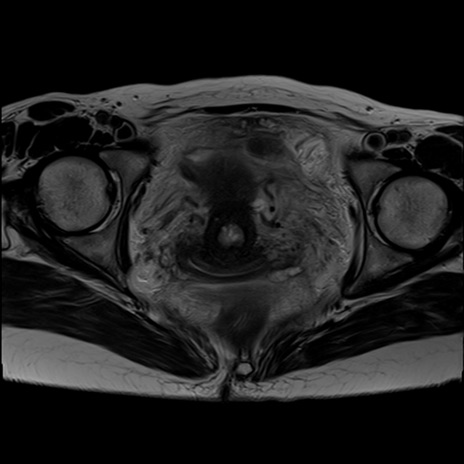

症例39 T2WI(横断像)

【症例】40歳代女性

【主訴】上下腹部痛

【現病歴】2日目から下腹部痛あり。夜間は痛みで眠れなかった。昨日より上腹部痛と下痢が出現。臥位で痛みは軽快したため、休んでいた。本日になって臥位でも立位でも痛みが強くなってきたため救急要請。

【既往歴】子宮内膜症

【身体所見】部:平坦・軟、左上下腹部に圧痛あり、反跳痛あり。

【データ】WBC 21800、CRP 26.78

MRI(4日後)